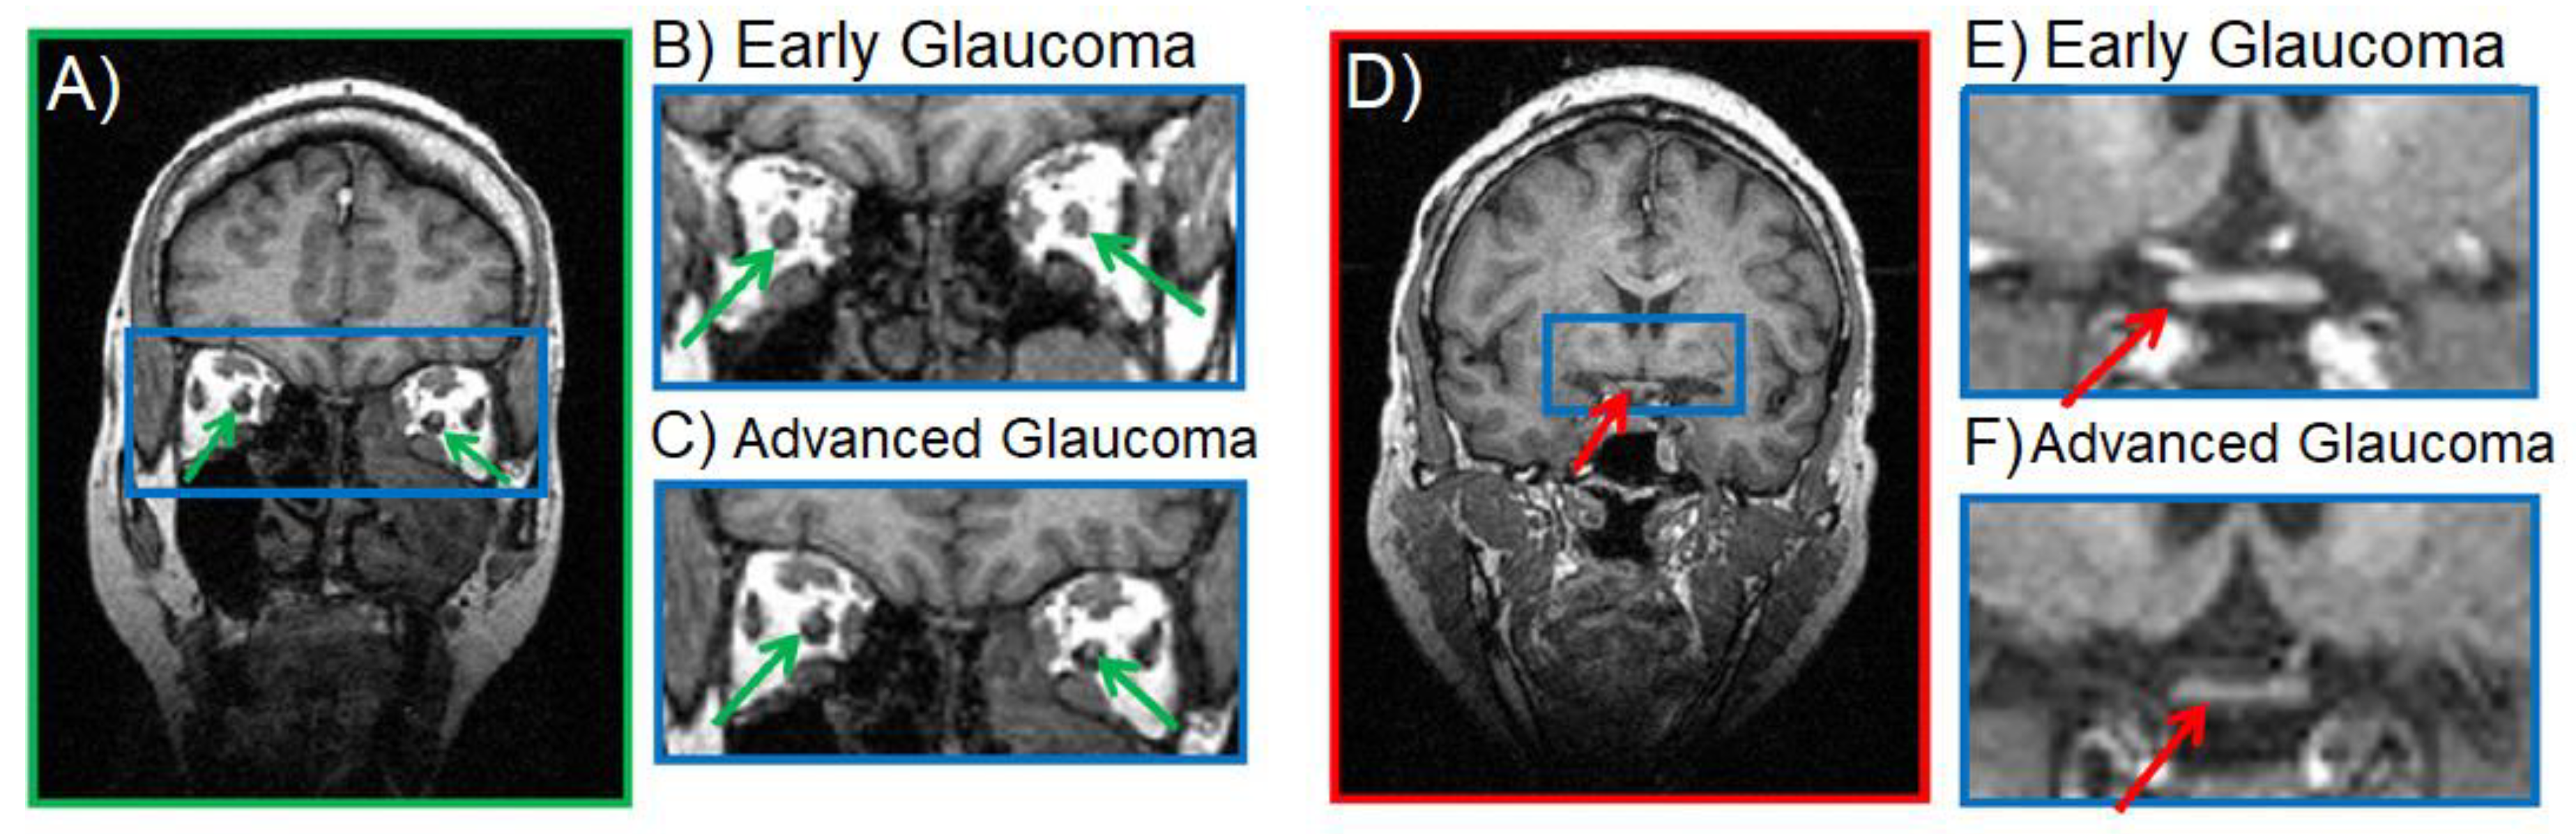

2.2. Anatomical MRI in Glaucona

- Dai, H.; Mu, K.; Qi, J.; Wang, C.; Zhu, W.; Xia, L.; Chen, Z.; Zhang, H.; Ai, F.; Morelli, J. Assessment of Lateral Geniculate Nucleus Atrophy with 3T MR Imaging and Correlation with Clinical Stage of Glaucoma. Am. J. Neuroradiol. 2011, 32, 1347–1353. [Google Scholar] [CrossRef] [PubMed] [Green Version]

- Gupta, N.; Greenberg, G.; De Tilly, L.N.; Gray, B.; Polemidiotis, M.; Yucel, Y.H. Atrophy of the lateral geniculate nucleus in human glaucoma detected by magnetic resonance imaging. Br. J. Ophthalmol. 2008, 93, 56–60. [Google Scholar] [CrossRef]

- Gupta, N.; Ang, L.-C.; De Tilly, L.N.; Bidaisee, L.; Yücel, Y.H. Human glaucoma and neural degeneration in intracranial optic nerve, lateral geniculate nucleus, and visual cortex. Br. J. Ophthalmol. 2006, 90, 674–678. [Google Scholar] [CrossRef]